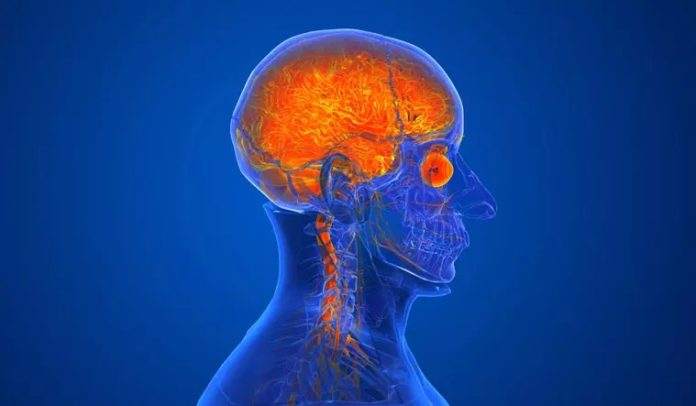

കോളിക്കോട്: താമരശ്ശേരിയിൽ ഒൻപത് വയസുകാരി മരിച്ചത് അമീബിക് മസ്തിഷ്ക ജ്വരം ബാധിച്ചെന്ന് സ്ഥിരീകരണം. കോഴിക്കോട് മെഡിക്കൽ കോളേജിലെ മൈക്രോബയോളജി ലാബിൽ നടത്തിയ പരിശോധനയിൽ അമീബിക് സാന്നിധ്യം കണ്ടെത്തി. നേരത്തേ പോസ്റ്റ്മോർട്ടത്തിൽ കുട്ടി മരിച്ചത് മസ്തിഷ്ക ജ്വരം ബാധിച്ചാണെന്ന് വ്യക്തമായിരുന്നു. ഇക്കാര്യം സ്ഥിരീകരിക്കാൻ കുട്ടിയുടെ സ്രവം പരിശോധനയ്ക്ക് അയച്ചിരുന്നു. സ്രവ പരിശോധനാ ഫലം പുറത്തുവന്നപ്പോഴാണ് കുട്ടിക്ക് അമീബിക് മസ്തിഷ്ക ജ്വരമെന്ന് വ്യക്തമായത്.കോഴിക്കോട് താമരശ്ശേരിയിൽ ഒൻപത് വയസുകാരി പനി ബാധിച്ച് മരിച്ചുഇന്നലെയായിരുന്നു കോരങ്ങാട് ആനപ്പാറ പൊയിൽ സനൂപിന്റെ മകൾ അനയ മരിച്ചത്. കോരങ്ങാട് എൽ പി സ്കൂളിലെ നാലാം ക്ലാസ് വിദ്യാർത്ഥിനിയായിരുന്നു. പനി മൂർച്ഛിച്ചതിനെ തുടർന്ന് കുട്ടിയെ ആദ്യം താമരശ്ശേരി താലൂക്ക് ആശുപത്രിയിലും പിന്നീട് കോഴിക്കോട് മെഡിക്കൽ കോളേജ് ആശുപത്രിയിലും പ്രവേശിപ്പിച്ചിരുന്നു. പിന്നീട് കുട്ടിയുടെ നില വഷളാകുകയും മരണം സംഭവിക്കുകയുമായിരുന്നു. കുട്ടിക്ക് മതിയായ ചികിത്സ ലഭിച്ചില്ലെന്ന് ആരോപിച്ച് കുടുംബം രംഗത്തെത്തിയിരുന്നു.എന്നാൽ കുട്ടിക്ക് ചികിത്സ ലഭ്യമാക്കിയെന്നാണ് താമരശ്ശേരി താലൂക്ക് ആശുപത്രി അധികൃതർ പ്രതികരിച്ചത്. പനി, ഛർദ്ദി ലക്ഷണങ്ങളുമായി എത്തുന്ന കുട്ടികൾക്ക് നൽകുന്ന ചികിത്സ അനയയ്ക്കും നൽകിയിരുന്നു. രക്തപരിശോധന അടക്കം നടത്തിയിരുന്നു

ഒൻപത് വയസുകാരി മരണം: മസ്തിഷ്ക ജ്വരം ബാധിച്ചെന്ന് സ്ഥിരീകരണം